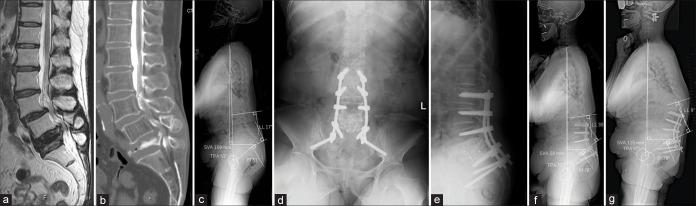

Three women, ranging in age from 69 years to 82 years, were surgically treated for a complete L5 OVBF. Two of these patients were being treated for rheumatoid arthritis. Surgery was performed using the L5 shortening osteotomy or vertebroplasty, with one- or two-level posterior lumbar interbody fusion, and posterior spinal fixation for the L2 or L3 to the pelvis. Although the spinal alignment parameters, which included lumbar lordosis (LL), pelvic incidence-lumbar lordosis, T1 pelvic angle, and sagittal vertical axis, were better as compared to that observed before the surgery, these worsened at the final follow-up due to clinical fractures that occurred at the adjacent vertebral body and proximal junctional kyphosis. Compared to preoperative Japanese Orthopaedic Association (JOA) scores, postoperative JOA scores were improved and maintained at the final follow-up.

三名年龄在69岁至82岁之间的女性接受了L5 OVBF的手术治疗。其中两名患者正在接受类风湿性关节炎治疗。手术采用L5缩短截骨术或椎体成形术,同时进行一或两节段的后路腰椎椎间融合术,并对L2或L3至骨盆进行后路脊柱固定。尽管包括腰椎前凸(LL)、骨盆入射角-腰椎前凸、T1骨盆角和矢状垂直轴在内的脊柱对线参数在术后较术前有所改善,但由于相邻椎体发生临床骨折和近端交界性后凸,这些参数在末次随访时恶化。与术前日本骨科协会(JOA)评分相比,术后JOA评分有所改善,并在末次随访时得以维持。